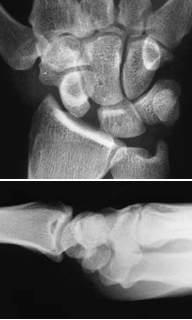

AP radiographs

Lateral